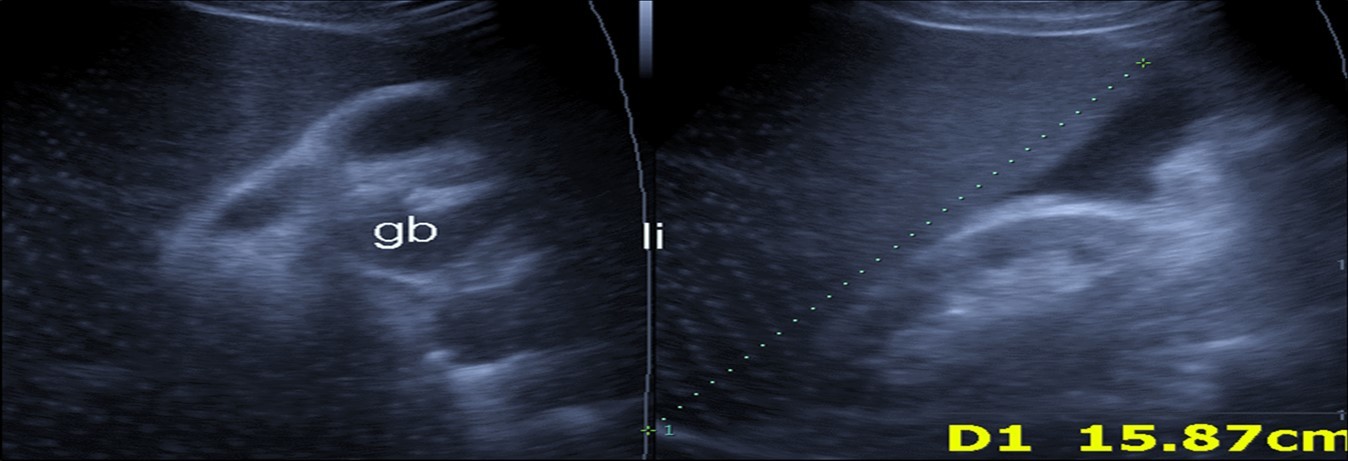

Figure 5.Real time ultrasound showing mild hepatomegaly (li), ascites and thickened gall bladder wall(gb).

Real time ultrasound showing mild hepatomegaly (li), ascites and thickened gall bladder wall(gb).

Abdominal ultrasound may revealed any of the followings:-Mild hepatomegaly with echogenic parenchyma and ascites in cases with hepatic impairment (Figure 4, Figure 5) ,thick walls of gall bladder with mildly dilated Common bile duct suggesting of biliary stasis and cholecystitis (Figure 6) .Abnormal renal echogenicity (Figure 7), suprarenal gland enlargements with heterogeneous texture ,splenic wedge shape area of hypoechogenicity ,thickened walls of bowel mainly the rectosigmoid region ,dilated bowel loops with free peritoneal fluid, and gases in the bowel wall with mesenteric and portal vein gases suggesting of bowel wall infarction13.